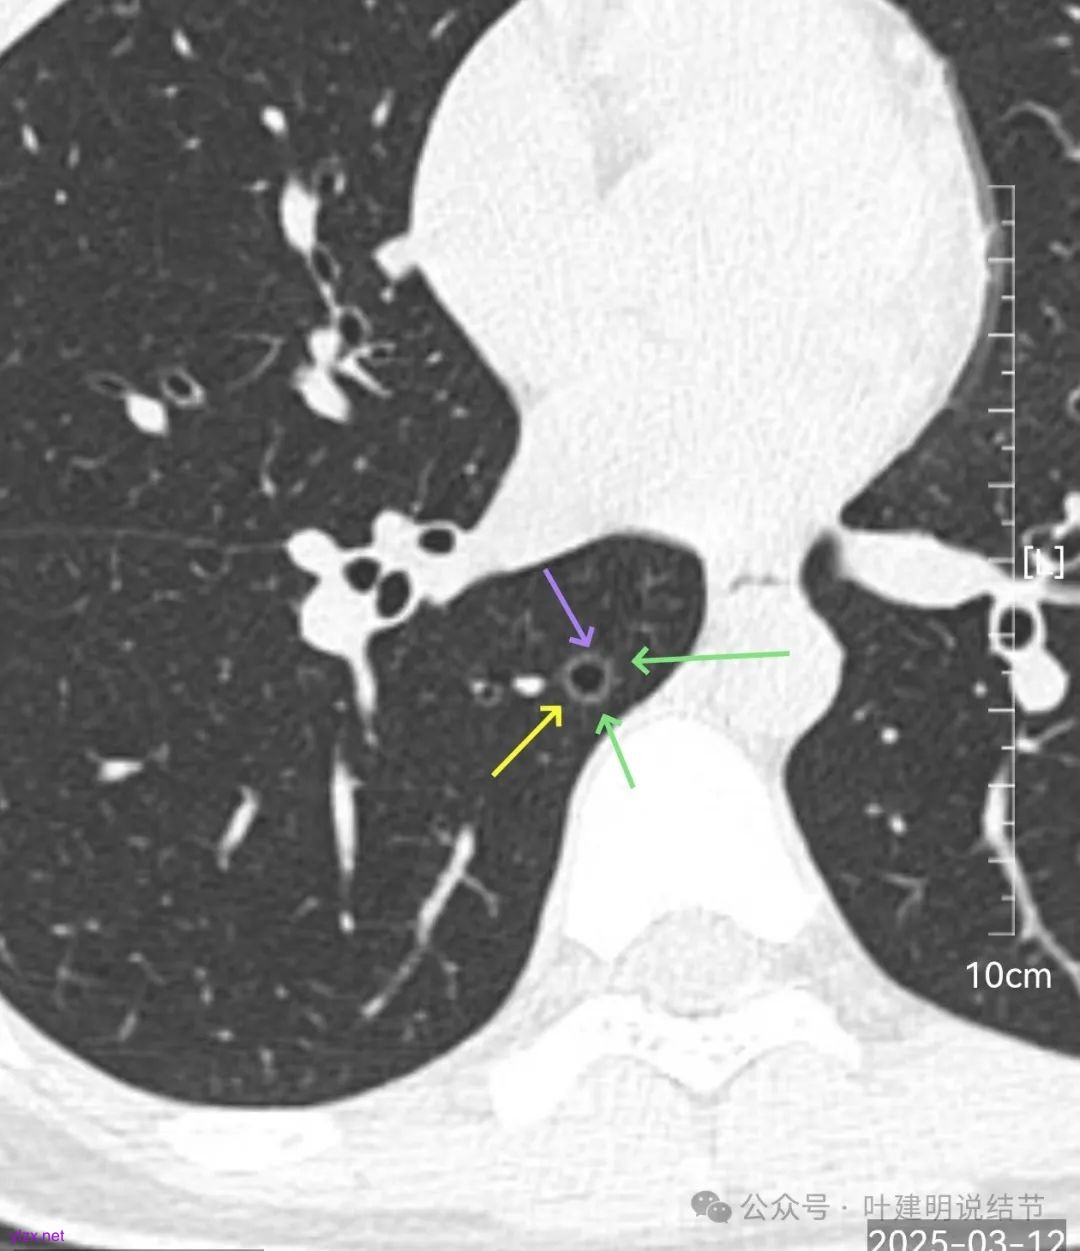

再来看风险最大的病灶6的连续层面:

血管从旁过,没有受结节影响。

两肺多发结节,均是磨玻璃密度,没有明显实性成分,主病灶有血管贴边,并伴空腔征,确实是囊腔型肺结节,而且考虑是肿瘤性质的,但囊壁没有实性成分,所以性质以应该是原位癌或微浸润性腺癌可能性较大,病理成分大概率仍是贴壁为主型(原位癌、微浸润性腺癌、浸润性腺癌贴壁亚型,这三类均是贴壁生长为主),所以风险低,进展慢的。对比2023年8月的也没有显著变化进展。其余结节均密度更淡或更小,风险性较主病灶更低,大概以肺泡上皮增生可能性较大,我觉得连不典型增生也不到的样子。所以总体上均考虑是广义上来说的肿瘤范畴,但危险性目前并不大。而且多发结节加上年轻,即使目前这些予以解决,后续再检查出新的磨玻璃结节的概率还是很大的,多处疤痕反而影响新增结节的观察与判断。我的想法是:目前不需要手术,可以9-12个月复查随访,若是有备孕计划,也可先备孕,等生了小孩再复查下就可以(间隔12-18个月一般关系也不会大)。至于消融,虽然许多医院与医生在推荐,但按目前的肺癌诊疗指南以及消融的专家共识,指征都是放在不宜手术(包括肺功能差、年纪大、曾经手术过、胸膜腔闭锁、全肺切除过等)或坚决拒绝手术的病人(比如宗教信仰或其他特殊原因),手术仍是首选的,尤其是位于外周能楔形切除的病灶的话,手术的创伤与对肺功能的影响并不大。我另外总结的消融弊端最主要有两点:一是肿瘤有没有完全灭活无法评估;二是消融后的疤痕区域肿瘤有没有复活无法评估。对于许多医生认为消融后3年或5年没有监测到病灶复发的说法,我是认为对于磨玻璃结节不处理许多也能5年,甚至10年不进展,用3年或5年的时间来评估有没有复发显然是不可靠的。意见供参考!